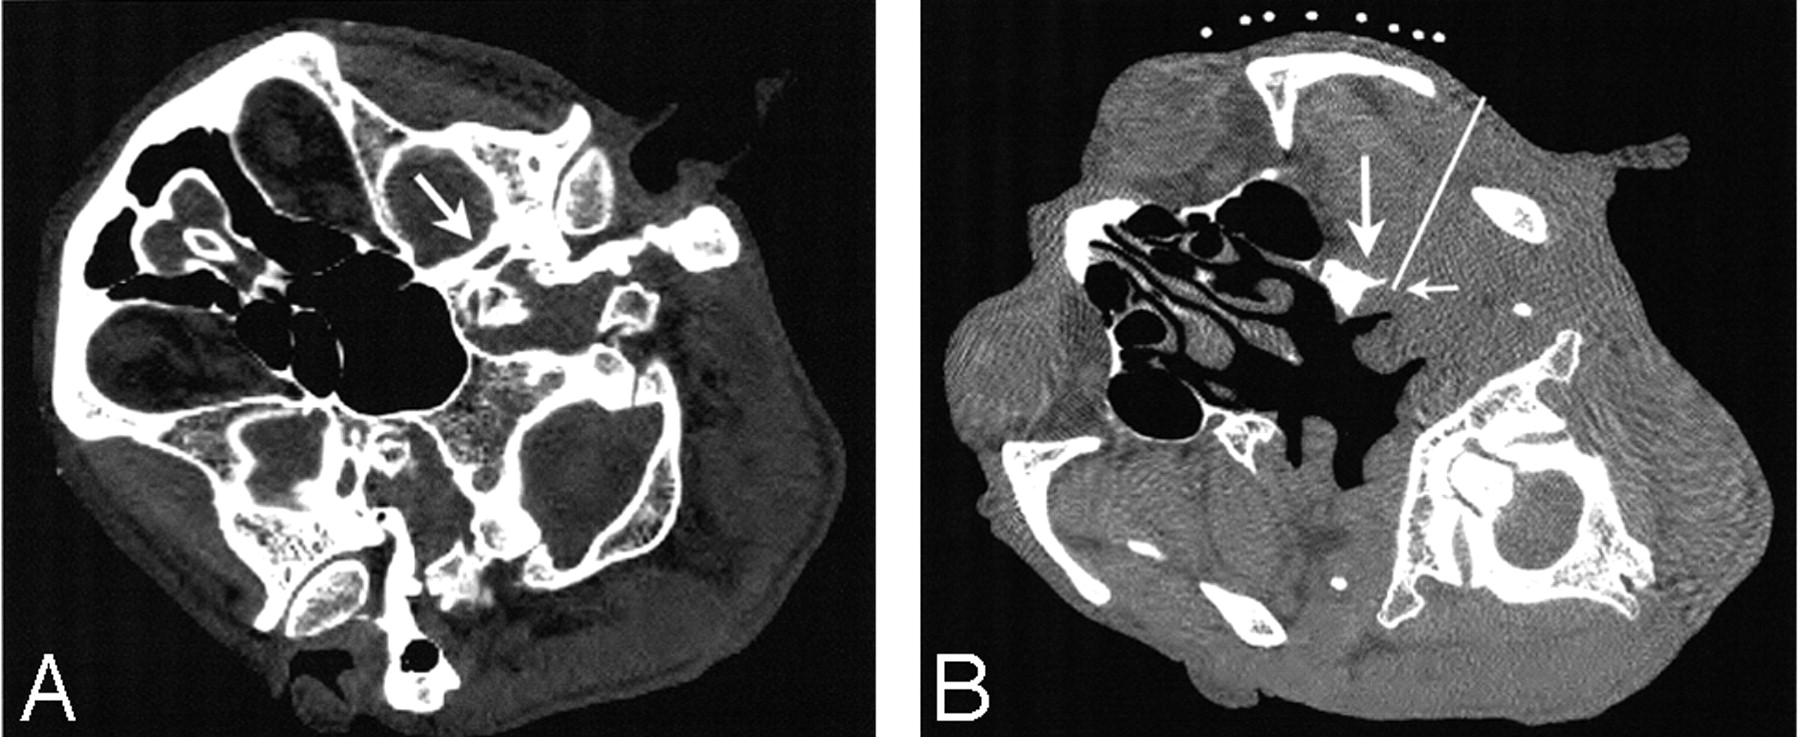

The patient was placed supine on a CT table in a lateral position with the diseased area up. A marking device made of X-ray opaque wires was attached to his ipsilateral cheek. The CT gantry (HiSpeed Advantage SG, GE Healthcare, Milwaukee, Wis) was set at an oblique position to obtain axial view sections of the base of the skull and foramen ovale. The needle insertion route was then designed as depicted in Fig 1. On these CT sections, the foramen ovale and posterior margin of the lateral pterygoid plate were clearly identified. The foramen ovale was a landmark on CT images in this patient, and the mandibular nerve immediately caudal to the foramen ovale in the posterior margin of lateral pterygoid plate was considered to be the target site. The distance between the insertion point and the target was 60 mm. The insertion point was marked with reference to the marking device.

Axial CT sections of the head. Arrow indicates foramen ovale (A), which is a landmark to identify the location of nerve exit from the cranium on CT images in this patient. The safest and shortest route (white line) to the target site (small arrow) is determined on the CT image (B, caudal section to A). The mandibular nerve immediately caudal to the foramen ovale in the posterior margin of lateral pterygoid plate (large arrow) is considered to be the target site.